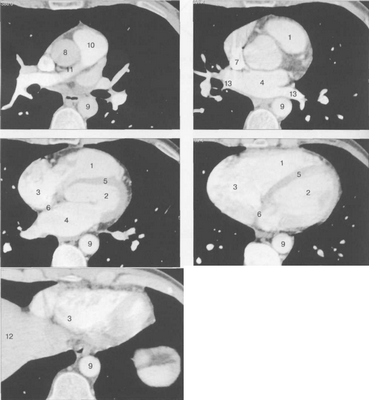

КТ-исследование позволяет получать поперечные (аксиальные) сечения сердца. Стандартная пошаговая КТ и даже спиральная КТ не получили распространения для исследования морфологии и функции сердца. Более тщательный анализ внутрисердечных структур возможен с помощью многослойной спиральной КТ (МСКТ) в условиях внутривенного контрастирования. КТ-изображения сердца и сосудов на различных уровнях представлены на рис. 9.34.

Рис. 9.34. КТ сердца и сосудов.

1 — правый желудочек; 2 — левый желудочек; 3 — правое предсердие; 4 — левое предсердие; 5 — межжелудочковая перегородка; 6 — межпредсердная перегородка; 7 — верхняя полая вена; 8 — восходящая часть аорты; 9 — нисходящая часть аорты; 10 — легочный ствол; 11 — правая легочная артерия; 12 — диафрагма; 13 — легочные вены.